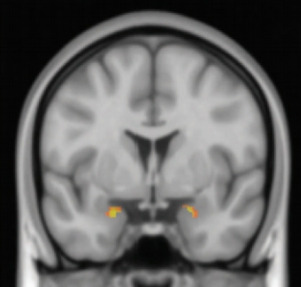

7eb12a0bf68cfd4593a64bf0d24e3da9.jpg

스웨덴 린코핑대 연구팀이 불안장애를 앓고 있는 환자들에게 인지치료를 진행한 결과, 뇌 편도체(사진에서 노란부분)의 부피가 줄고, 활성도 진정됐다. 노란색에 가까울수록 뇌의 산소포화도가 높아 뇌 활성이 활발하다는 뜻이다. 중개정신의학 제공

불안과 공포처럼 코로나19가 불러온 부정적 감정 변화는 해마 끝부분에 연결된 편도체가 주관한다. 공포나 불안은 편도체를 포함한 주위 영역을 활성화하는데, 평소 편도체와 연결돼있는 전전두피질이 이렇게 활성화된 영역들을 진정하도록 유도한다. 하지만 공포와 불안 자극이 지속되면서 편도체의 활성화가 불안장애 수준으로 심해지면, 편도체와 전전두피질의 연결이 약해져 편도체의 활성화를 효과적으로 진정시킬 수 없게 된다.

다행스러운 것은, 이런 변화가 회복이 불가능한 영구적인 변화는 아니라는 것이다. 감정에 의해 뇌 건강이 악화될 수 있다는 것은, 거꾸로 감정을 조절하면 뇌 건강을 낫게 할 수 있다는 뜻이기도 하다. 크리스토퍼 맨슨 스웨덴 린코핑대 심리학과 연구원팀은 불안장애를 치료하기 위한 인지치료가 편도체 회색질 부분의 부피를 줄인다는 연구결과를 2016년 국제학술지 ‘중개정신의학’에 발표했다. 인지치료는 현재 대부분의 정신건강의학과 질환에서 가장 효과적인 비약물적 치료로 인정받는 치료법으로, 생각을 변화시킴으로써 감정을 다스리도록 유도한다.

연구팀은 불안장애를 앓고 있는 환자 26명을 대상으로 9주간 인지치료를 진행했다. 그리고 인지치료 전과 후 환자들의 뇌를 기능적자기공명영상(fMRI)으로 분석했다. 그 결과, 인지치료 이전에 비해 이후에 편도체 회색질 부분 부피가 줄어들었다는 사실을 확인했다. 편도체 신경세포의 반응도도 감소했다. 연구팀은 불안장애 환자의 편도체가 과도하게 활성화돼 부피와 반응도가 늘어난 상태였으며, 인지치료가 편도체를 진정시켜 이 같은 결과가 나왔다고 해석했다. doi: 10.1038/tp.2015.218